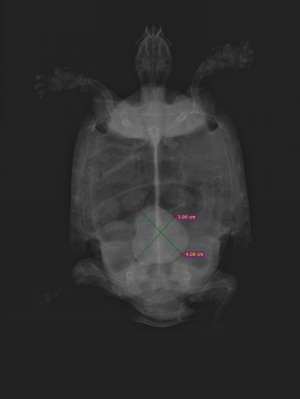

レントゲン検査の結果、お腹の中に巨大な結石を確認。

血液検査で腎障害も認められたため、開腹手術を実施することとなりました。